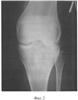

Способ проиллюстрирован сделанными в процессе лечения рентгенограммами нижней левой конечности (в разогнутом состоянии) больной М.:

Фиг.3 – интраоперационная после остеотомий при фиксации костно-хрящевого фрагмента П-образно изогнутой спицей;

В СарНИИТО 13.12.05 было проведено оперативное вмешательство по запланированной схеме (фиг.5). Произвели дугообразный разрез по передневнутренней поверхности проксимального отдела левой голени длиной 12 см. В верхней трети левой большеберцовой кости выполнена корригирующая многоплоскостная остеотомия с формированием внесуставно костно-хрящевого суставного фрагмента. На задней поверхности голени вырезали клин углом в 10° и шириной 8 мм. Затем была пересечена в средней трети малоберцовая кость. Проведенными в сагиттальной плоскости П-образно изогнутой спицей Киршнера и стержнем костно-хрящевой фрагмент зафиксирован в аксиальной плоскости. Интраоперационно под рентгеноконтролем на голень наложен двухсекционный спице-стержневой аппарат внешней фиксации (фиг.4). Спица и стержень закреплены на верхней базовой опоре аппарата посредством тяговых устройств.